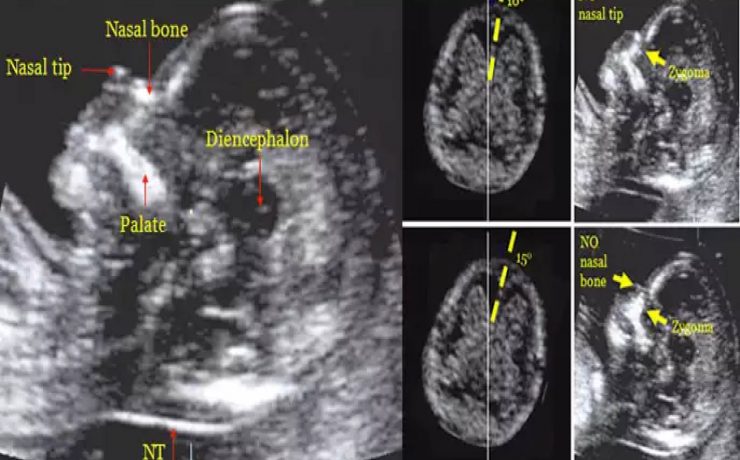

El objetivo del presente artículo es demostrar que la medición ecográfica del cordón umbilical es un factor que puede predecir la macrosomia fetal. Para lo cual se llevo a cabo un estudio descriptivo, observacional en mujeres gestantes a término cuyos factores de inclusión fueron gesta de 37 semanas, producto único